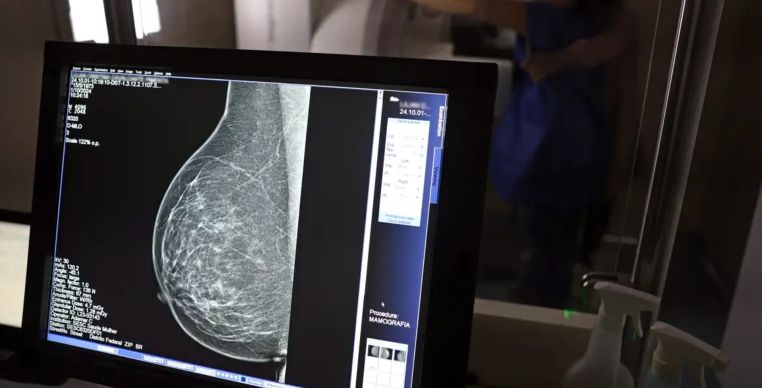

Foto: José Cruz / Agência Brasil

Mais de 108 mil mulheres com menos de 50 anos foram diagnosticadas com câncer de mama no Brasil entre 2018 e 2023, segundo análise do Painel Oncologia Brasil feita pelo Colégio Brasileiro de Radiologia e Diagnóstico por Imagem (CBR). Isso representa aproximadamente uma em cada três pacientes diagnosticadas com a doença no período.

Para a entidade, os dados reforçam a necessidade de ampliar o rastreamento do câncer de mama por meio da mamografia também em mulheres com menos de 50 e mais de 70 anos, atualmente fora da recomendação padrão para exames preventivos pelo Sistema Único de Saúde (SUS).